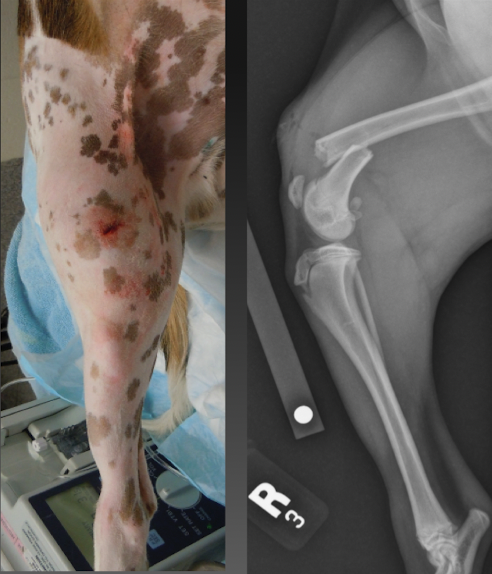

type III open fracture

extensive soft tissue damage with devitalization

major contamination

high energy trauma: gun shot

lots of pieces

outside to inside trauma

type IIIb open fracture

ST loss and inadequate ST coverage with periosteal

stripping and exposure of bone